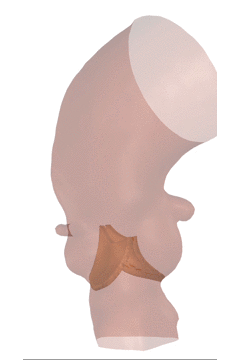

植入瓣膜前的瓣膜形态

VenusA植入后的瓣膜形态